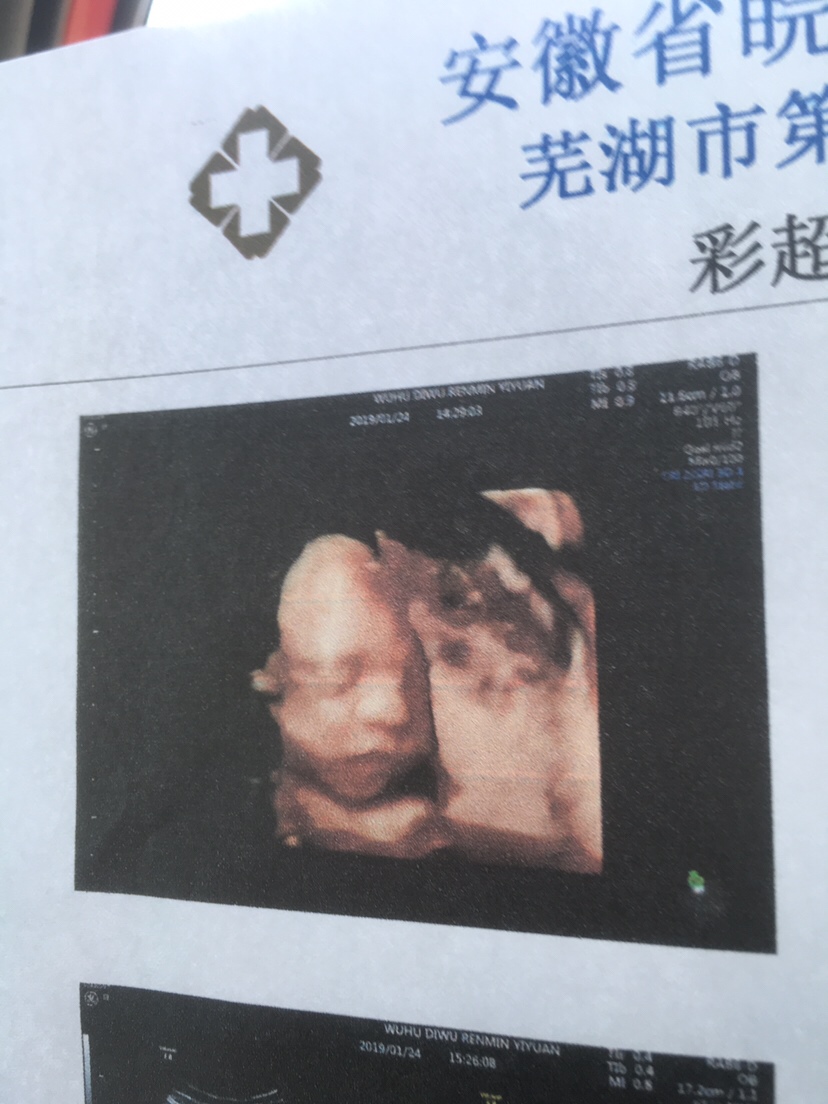

孕23周+1天

我今天才做的 全程医生一句话没有哈哈哈哈哈

拍得很清晰

好[帖主]:拍的很满意了 因为我比较胖